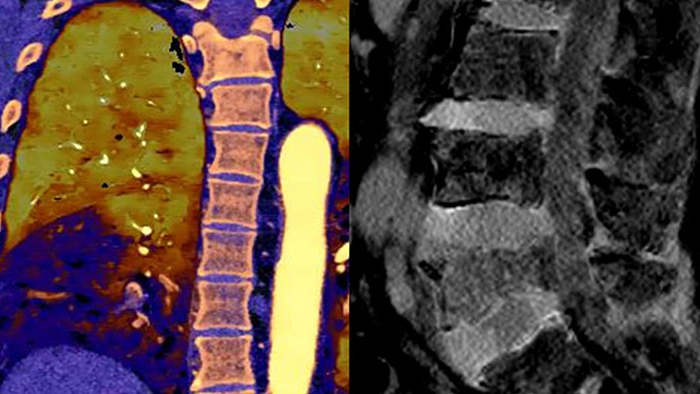

Spectral CT 7500 provides advanced diagnostic capabilities through a single spectral scan, enabling accurate diagnoses and expediting treatment times. Expand patient care with a one-stop solution across radiology, cardiology, oncology, neurology and trauma. Easy workflow with high image quality, low dose and spectral results. Scan in seconds as you normally would for conventional CT with immediate access to spectral CT results that can help eliminate the need for multiple CT scans or even additional scans from other modalities.

certainty of cyst vs. lesion compared to 30% with conventional CT2

With Spectral CT 7500, a single spectral scan offers advanced diagnostic capabilities to help speed time to treatment. Expand patient care with a one-stop solution across radiology, cardiology, oncology, neurology and ED/trauma.

Detector-based spectral allows the coronaries and myocardium to be assessed in a single exam. Spectral CCTA results can mean that patients avoid an invasive and expensive procedure in the cath lab. Perform comprehensive cardiac evaluations quickly, including perfusion and delayed enhancement studies, all without increased radiation dose

Detector-based spectral results can save the costs of repeat scans and contrast media, and potentially avoid scans from other modalities.

Radiodiagnóstico Resonancia Magnética Clinic Hospital Nuestra Señora del Rosario Madrid, Spain“Spectral imaging creates clear added value in diagnostics. We see more. And what we may have seen before, we can now say what it is with greater certainty. We also have the complete spectral information available.“